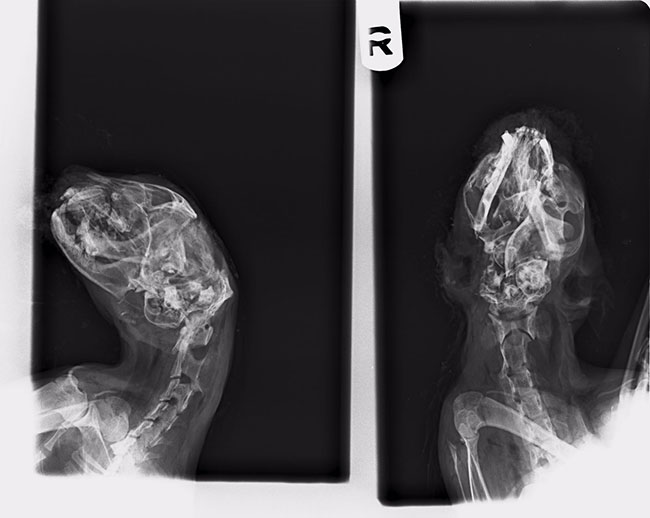

Una voluntaria se personó en la zona del delito, tras hablar con varios vecinos indicaron que el gato era un animal sociable que se arrimaba a la gente, entraba y salía de las parcelas. El cuerpo del animal fue trasladado a la clínica veterinaria dónde certificaron que había fallecido por un golpe en la cabeza, presentaba severo traumatismo cráneo encefálico con profusión ocular, que debió producirse en un sitio cercano donde estaba el animal ya que las lesiones eran incompatibles con la vida.